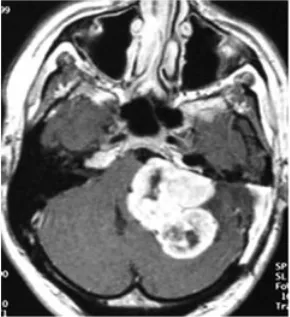

随后,患者再度出现面部麻木感与共济失调症状。此次磁共振检查结果令人警惕:肿瘤体积出现了显著扩大。临床团队判断肿瘤的生物学行为已发生根本性改变,遂实施根治性切除手术。

术后病理报告带来了最坏的消息:肿瘤已转化为恶性外周神经鞘膜瘤。免疫组化染色结果显示,此前在肿瘤细胞中呈弥漫阳性分布的S100蛋白,此时已变为仅灶性阳性,提示肿瘤细胞正在经历去分化过程。

然而恶化的速度远超预期。根治性切除手术后不过三个月,肿瘤即以极强的侵袭性迅速复发,并对脑干造成严重压迫。为维系基本生命功能,患者紧急接受了第二次手术以实施脑干减压。这一次的病理结果表明,肿瘤已进一步去分化,转化为间变性软组织肉瘤,神经源性标记物S100蛋白的表达已完全丧失。